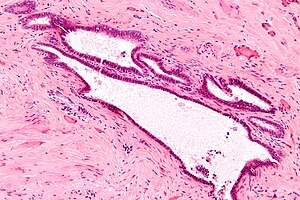

Endosalpingiosis. H&E stain.

LM cystic lesion with ciliated epithelium surrounded by fibrous stroma, psammoma bodies

• Cystic lesions with:

• Ciliated (tubal type) epithelium, without endometrial stroma.

• Endosalpingiosis is surrounded by fibrous stroma; tubal type epithelial surrounded by ovarian stroma is a variant of endometriosis.

• Associated with psammoma bodies.[5]